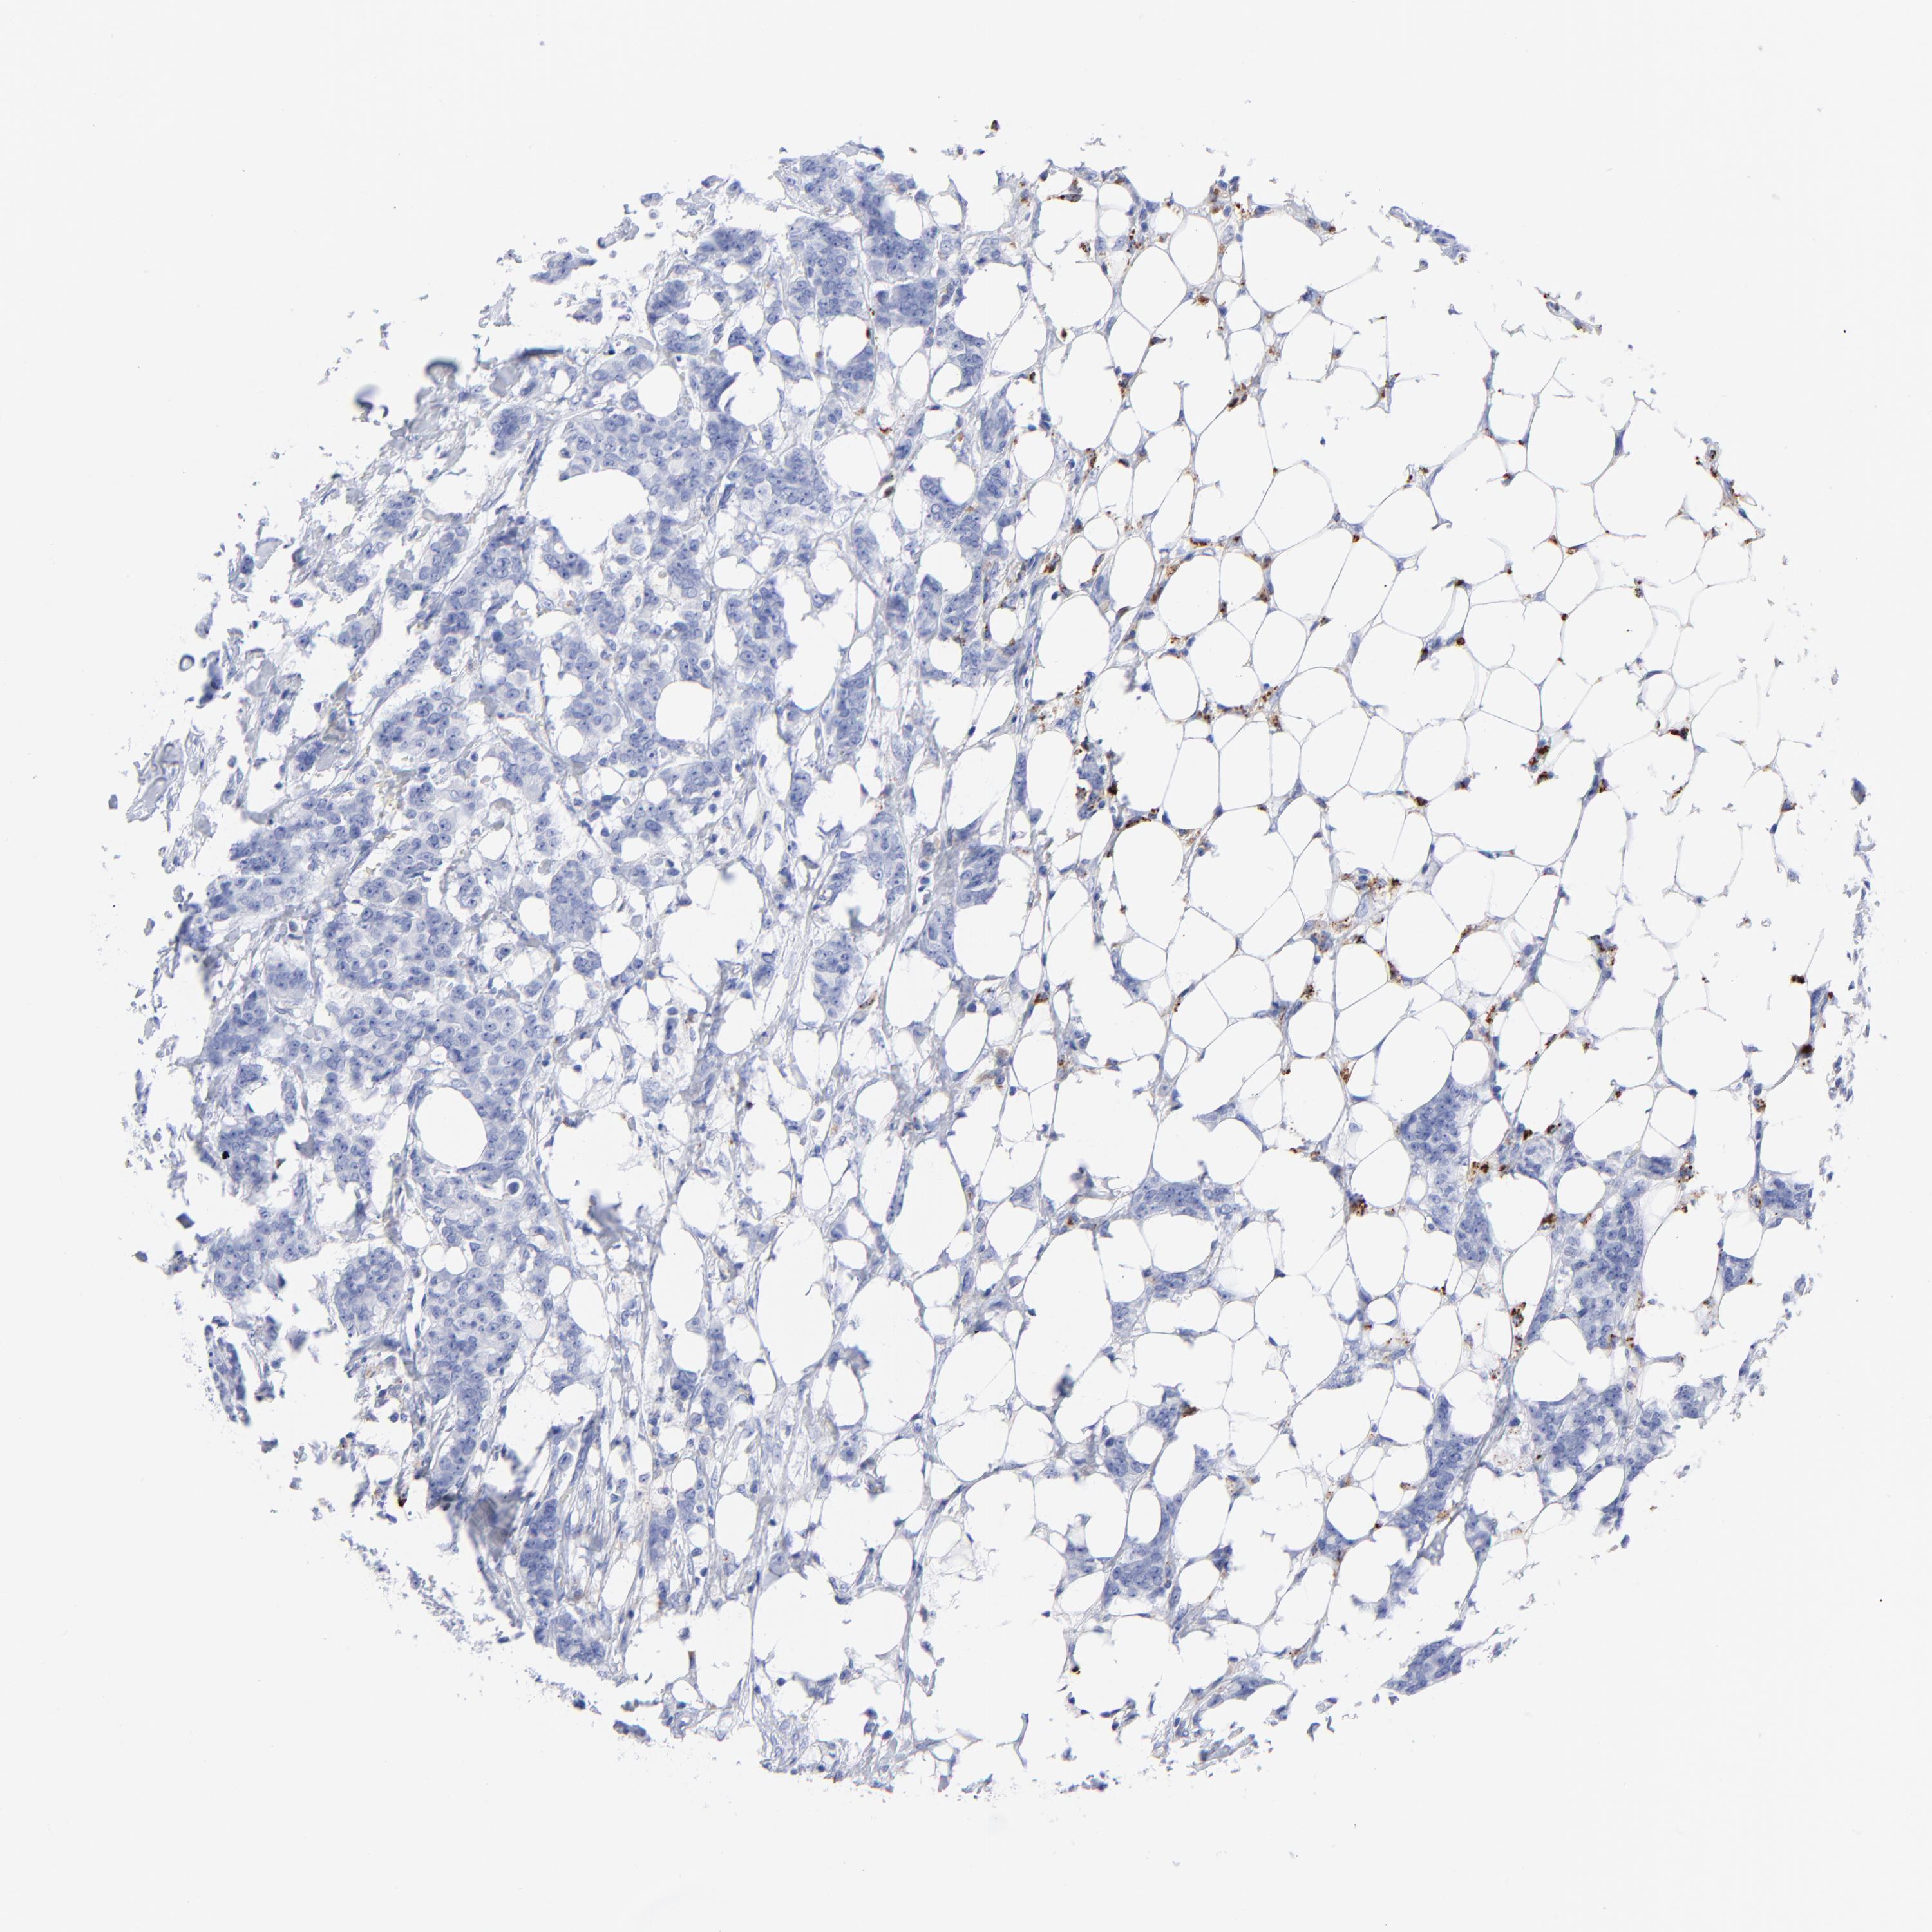

CANCER BREAST CANCER Show tissue menu

BRCA TCGA BRCA VALIDATION PROTEIN EXPRESSION